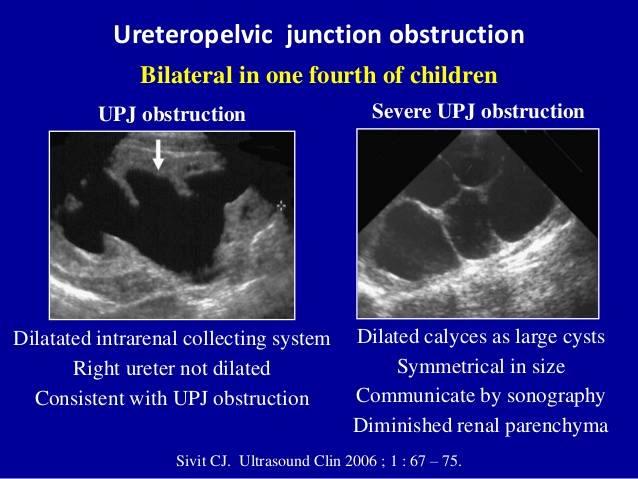

What is UPJ?

uritopelvis junction

What is ureteropelvic junction obstruction?

Obstruction of the urinary outflow. Can be acquired or congenital.

obstruction at the confluence of the kidney and the ureter

Sporadic

What is the most common cause of hydronephrosis in neonates?

UPJ obstruction

UPJ obstruction

UPJ obstruction

What is the sonographic appearance of ureteropelvic junction obstruction?

will often show a dilated renal pelvis

Doppler: Kidney w/higher resistive indices

hyperechoic kidneys